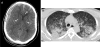

We report two patients that developed severe thrombocytopenia after Zika virus (ZIKV) infection. The first patient had 1000 platelets/μL and died after multiple hemorrhages. The second patient had 2000 platelets/μL, had melena and ecchymoses, and recovered after receiving intravenous immunoglobulin. ZIKV may be associated with immune-mediated severe thrombocytopenia.